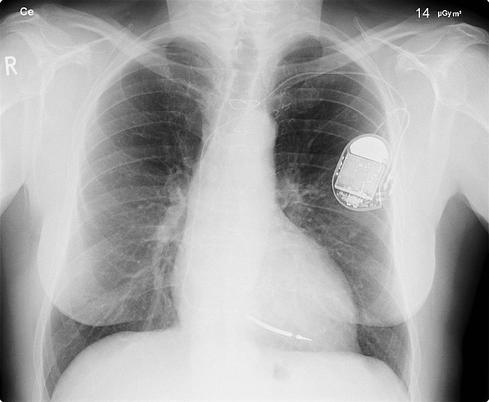

Hackers Outsmart Pacemakers, Fitbits: Worried Yet?

(click image for larger view)

(Source: Sh4rp_i, Flickr)